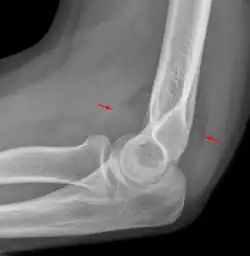

The fat pad sign, also known as the sail sign, is a potential finding on elbow radiography which suggests a fracture of one or more bones at the elbow. It may indicate an occult fracture that is not directly visible. Its name derives from the fact that it has the shape of a spinnaker (sail).[1] It is caused by displacement of the fat pad around the elbow joint. Both anterior and posterior fat pad signs exist, and both can be found on the same X-ray.

In children, a posterior fat pad sign suggests a condylar fracture of the humerus. In adults it suggests a radial head fracture.

The fat pad sign is invaluable in assessing for the presence of an intra-articular fracture of the elbow. An anterior fat pad is often normal. However a posterior fat pad seen on a lateral x-ray of the elbow is always abnormal. The patient will be unable to flex their elbow and requires orthopaedic input.[2]

The posterior fat pad is normally pressed in the olecranon fossa by the triceps tendon, and hence invisible on lateral radiograph of the elbow.[3] When there is a fracture of the distal humerus, or other pathology involving the elbow joint, inflammation develops around the synovial membrane forcing the fat pad out of its normal physiologic resting place. This is visible as the "posterior fat pad sign" and is often the only visible marker of a fracture, particularly in the pediatrics population.